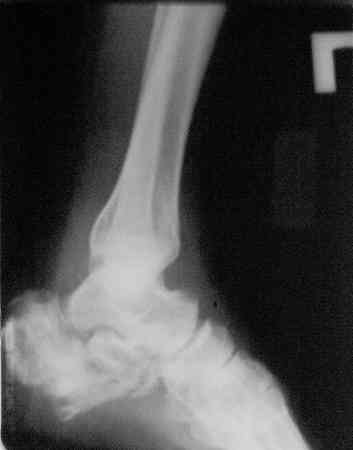

Здравствуйте,коллеги!Все оказалось даже хуже!Сегодня больной госпитализирован и:

С левой стопой дело похуже. Нужен прямой снимок, да и боковой не помешает повторить на всю стопу, ну и плюс аксиальный. Готовтье аппарат.

Отправляю снимки(свежие)и фото стоп.

С уважениемД.Б.